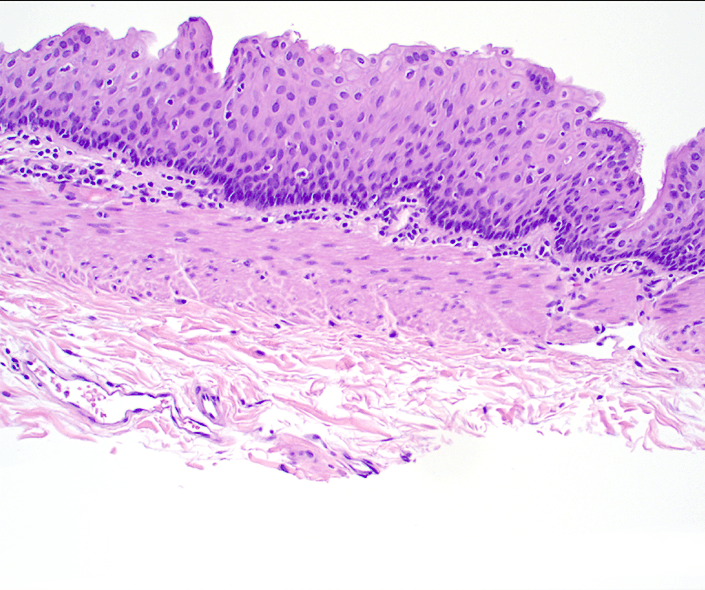

Microscopic findings

Cystic structure with a discrete muscular lining and an epithelial surface variably composed of nonkeratinizing squamous epithelium and ciliated, pseudostratified columnar epithelium with subepithelial seromucinous glands.

Figure 3. A different area of the cyst lining shows non-keratinizing stratified squamous mucosa with a thinned, but distinct underlying muscularis propria(20x).